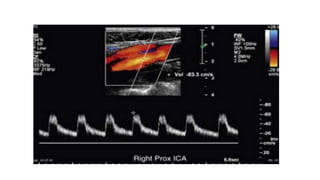

• Spectral Doppler tracings from the proximal CCA, distal CCA, proximal ICA,

mid ICA, distal ICA, proximal ECA, and mid vertebral artery.

• PSV is recorded for each segment, and end-diastolic velocity (EDV) is noted if it

is more than 100 cm/sec.

• The PSVR is calculated by dividing the highest PSV in the proximal ICA or area

of stenosis by the PSV in the distal CCA.

• PSV in the distal CCA should always be measured 2 to 3 cm proximal to the

level of the carotid bulb.

• Several measurements, optimally three, of PSV should be obtained and the

highest velocity recorded.

PSV- 195 CM/SEC PSV-96CM/SEC

PSV- 195 CM/SECPSV-96CM/SEC

• #19 Normal spectral Doppler tracing of the internal carotid artery. Note that in comparison to the ECA, there is increased diastolic flow, the systolic peak is slightly blunted, and the spectral envelope is slightly widened in the ICA. The systolic upstroke is sharp, and velocity gradually tapers during diastole.